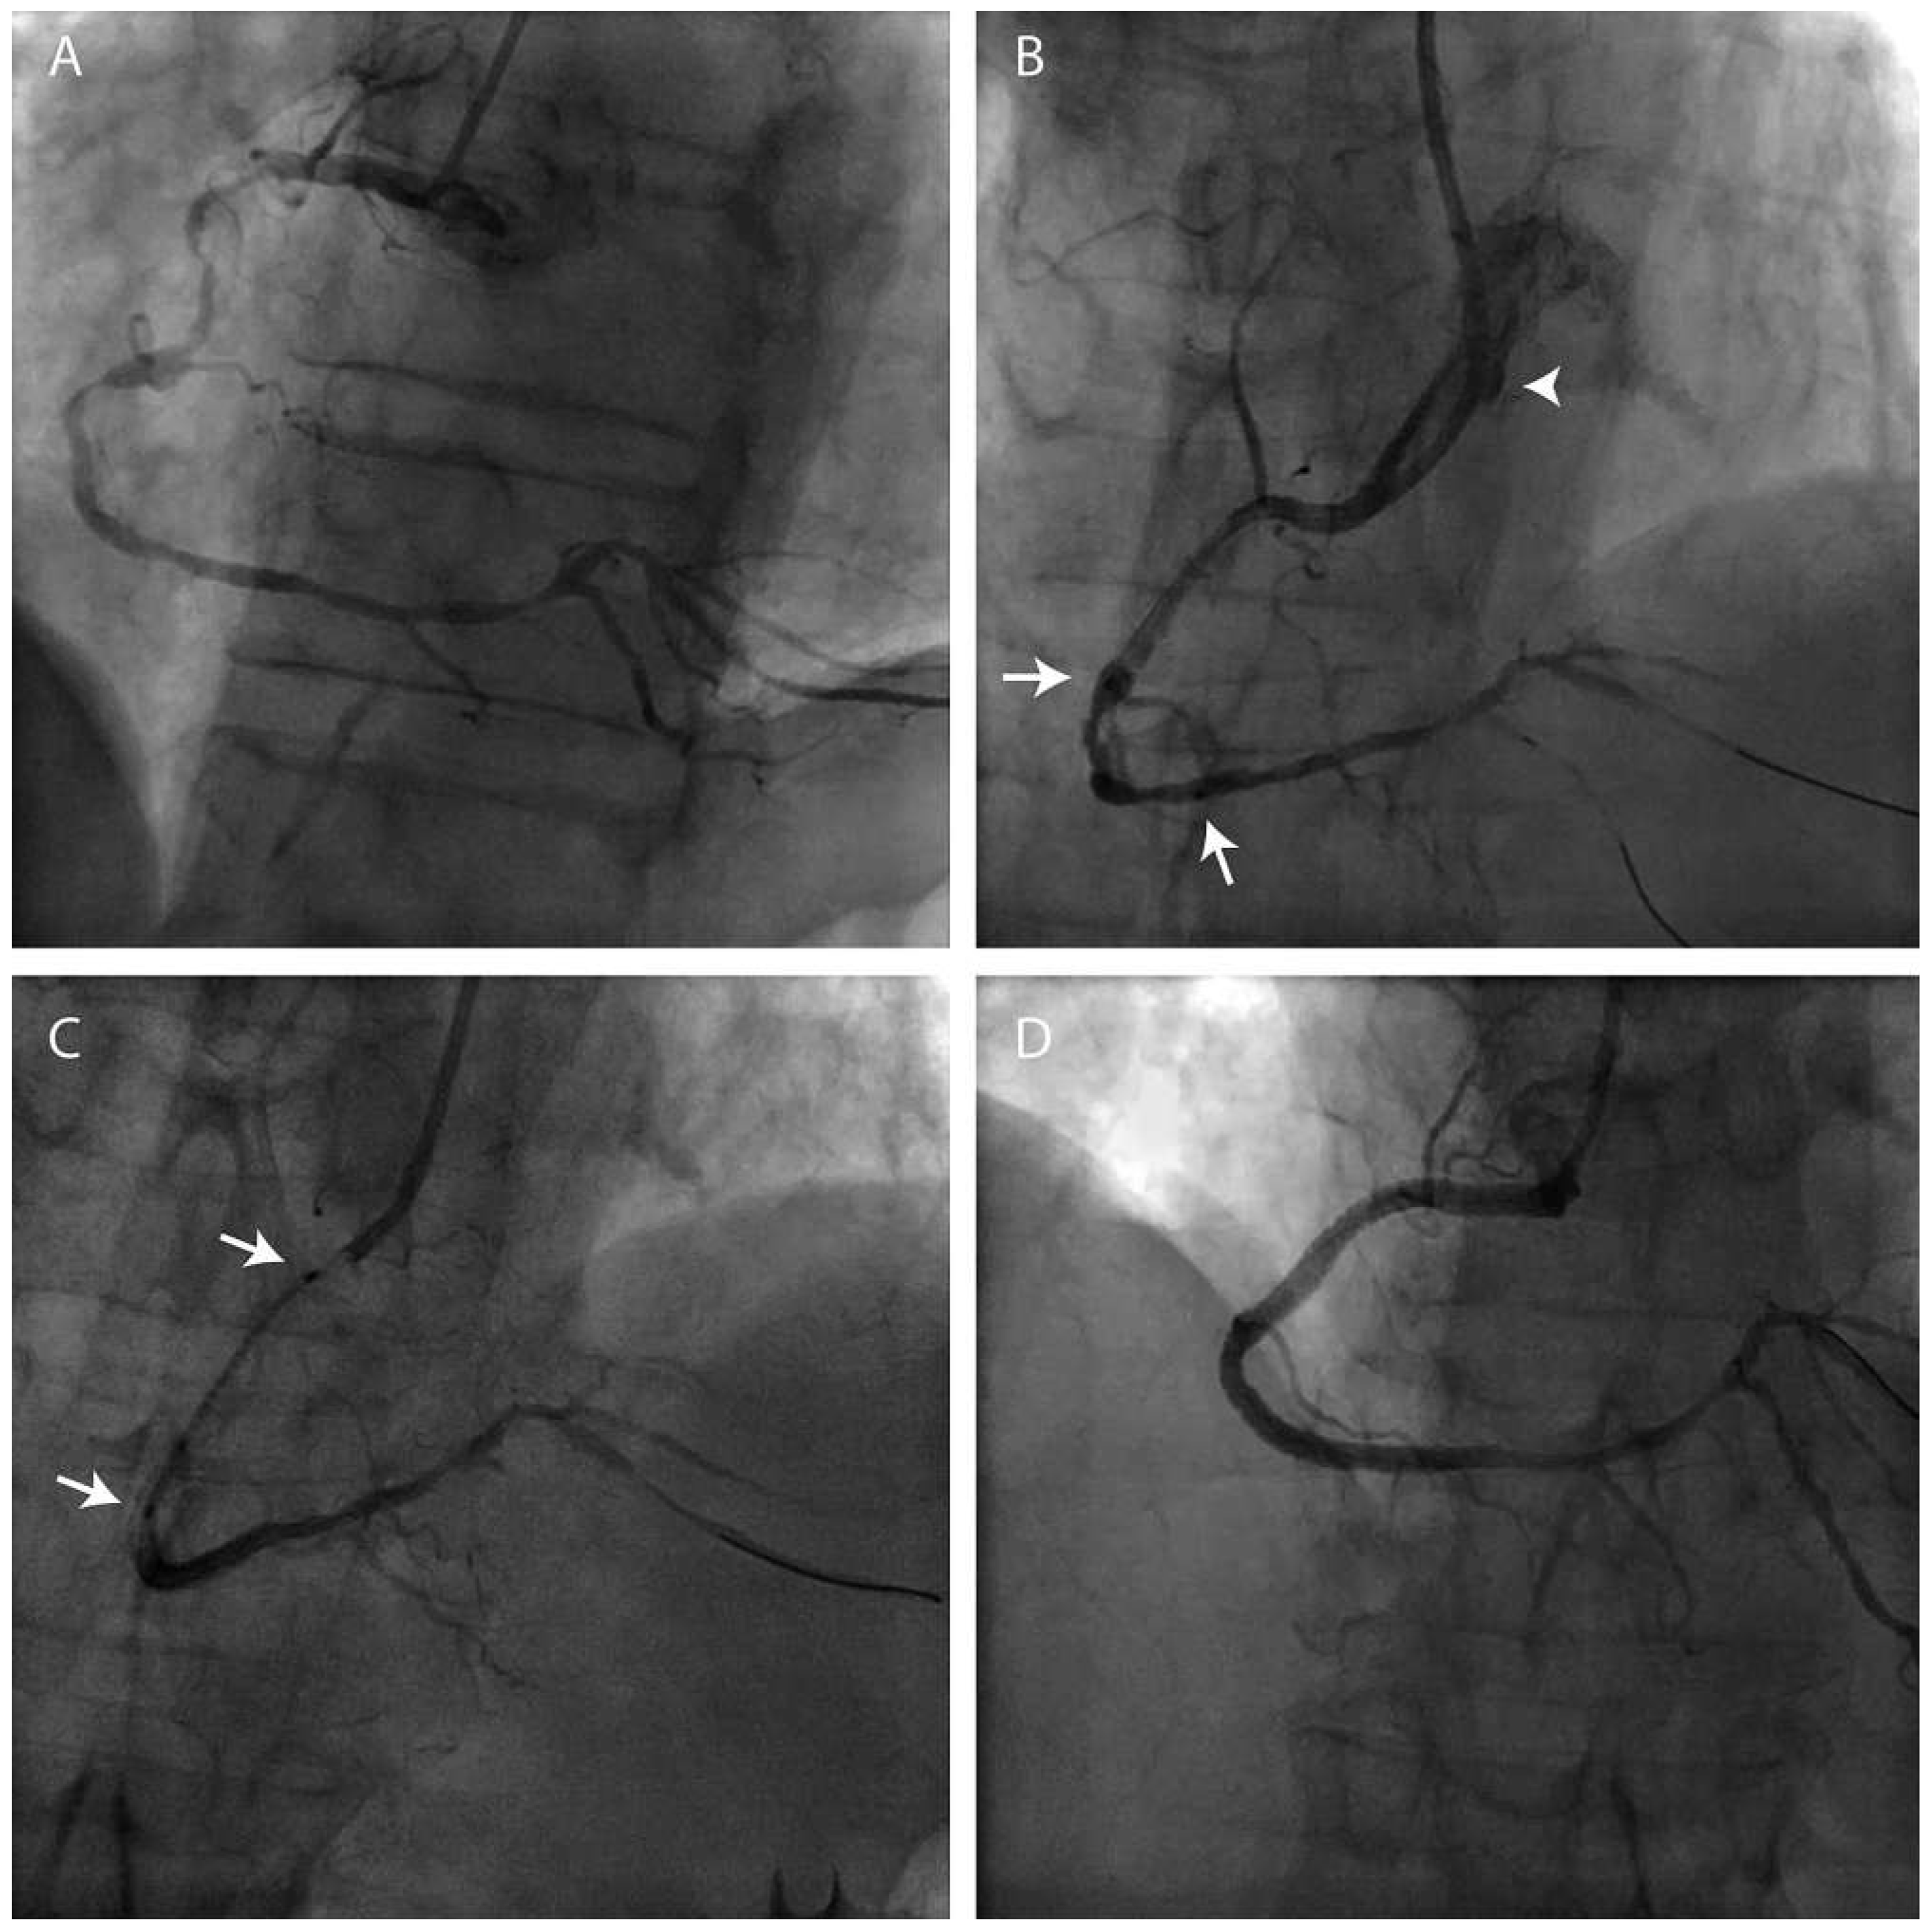

Patients with coronary artery bypass grafts (CABG)

- Burzotta, F.; Trani, C.; Hamon, M.; et al. Transradial approach for coronary angiography and interventions in patients with coronary bypass grafts : Tips and tricks. Catheter Cardiovasc Interv. 2008, 72, 263–72. [Google Scholar] [CrossRef] [PubMed]